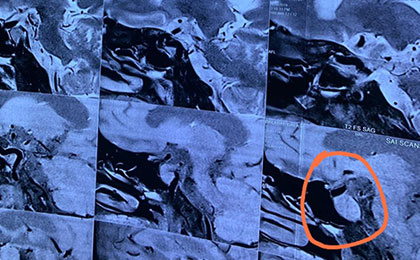

These are brain tumours found at the base of skull, they present with headache, visual disturbance and hormonal problems. They are diagnosed by CT or MRI brain And visual or hormonal test They are removed by surgery. We at lifeline hospital remove them endoscopically through nose, it gives faster recovery It is one of the advances in neurosurgery. Last week we removed three such large brain tumours ( pituitary), all patients doing well, with the help of government scheme, with minimal expenses.

These are mri pictures and operative video.